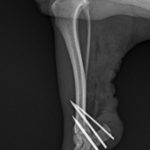

アキレス腱断裂 主治医よりアキレス腱断裂した患者さんが脚を着けなくなったので、なんとかして欲しいと連絡がありました。経関節ピンによる一時的な足根関節の仮固定とアキレス腱の縫合術により対応しました。しばらくは安静が必要です。 症例カテゴリー 放射線治療整形外科軟部組織外科脳神経外科内科腫瘍外科救急・集中治療リハビリテーション科腫瘍内科内視鏡科脳神経科呼吸器外科中医・漢方猫の腎移植循環器科